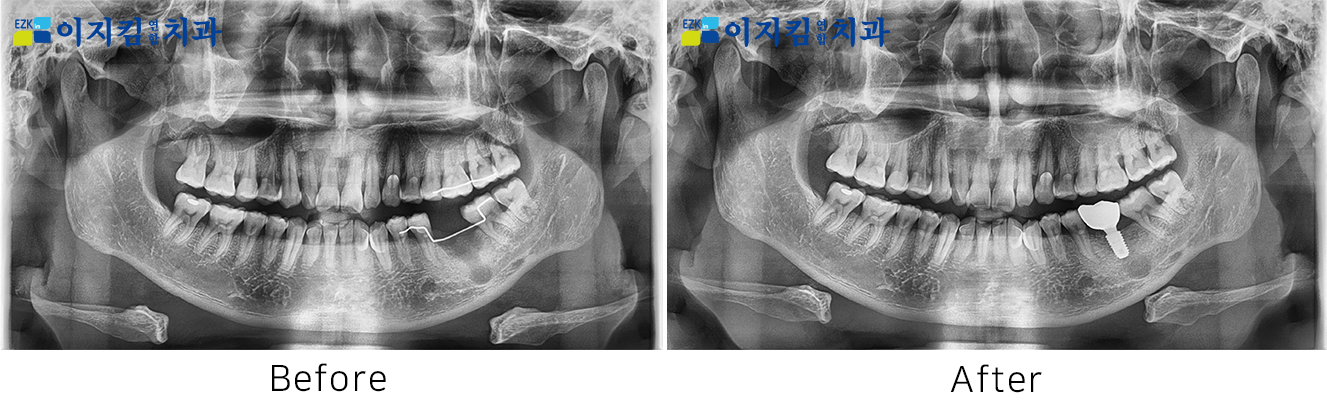

ÀÓÇöõÆ® Àü ¡¤ ÈÄ »çÁø